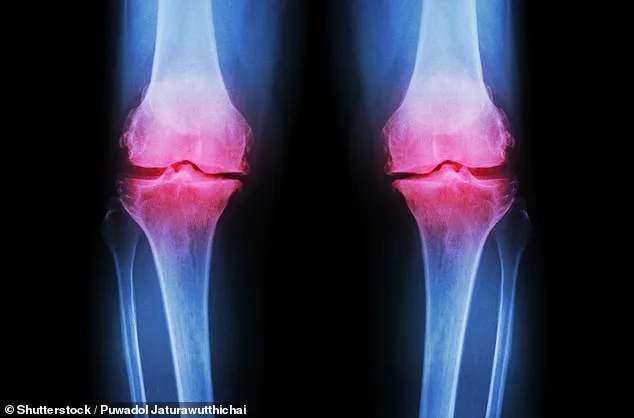

Osteoarthritis, a condition affecting millions globally, is typically associated with aging. Yet, its presence is now being diagnosed in younger populations at an unprecedented rate. By the age of 70, roughly half of all individuals will develop arthritis, but experts warn that the trend is shifting. In the UK alone, around 10 million people live with osteoarthritis, and younger generations are increasingly being affected. The condition arises when the cartilage that cushions joints deteriorates, leading to pain, stiffness, and mobility issues. While factors like genetics, obesity, and injury contribute to this decline, the role of extreme exercise and poor dietary habits in accelerating the process cannot be overlooked.

Post-traumatic osteoarthritis, a subset of the condition, often results from fractures that extend into joints. These injuries can disrupt normal joint mechanics, causing cartilage to break down more rapidly. However, unlike osteoporosis—where fragile bones significantly increase fracture risk—osteoarthritis can be mitigated through lifestyle adjustments. The challenge lies in the fact that many young people remain unaware that their exercise and diet choices can exacerbate their risk. For instance, the exclusion of dairy products in 'clean eating' diets is leading to calcium deficiencies, which weaken bones and increase inflammation.